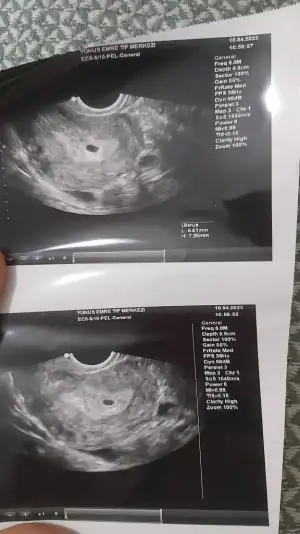

4 gün önce 4+6, iken alttan muayeneyle gordum canımBende hele bugün hiç bişi yok keseyi ne zaman gördün?

Adete göre saymıyor mu? Ben şuan 5+1 oluyorum pazartesi 4+5 de gördüm. Senin kese fotisi var mı? Atsana4 gün önce 4+6, iken alttan muayeneyle gordum canım

Keseyi 1500 sonrası görebilirmişsin 4+1 de görmüştük biz 1668 ile.

13 Mart adet günümün ilk günüydü. 27 martta aşılama oldum 9 Nisan da test pozitif gördüm pazartesi 10 Nisan da kan verdim 627.2 çıktı canım çarşamba verdim 1447.67 çıktı doktorum cuma keseyi görürüz dedi yarın gideceğimBeta ve gününüz kaç acaba?ben de Cumartesi başka bir doktordan randevu aldım kese için kendi doktorum daha bakmak istemedi. Benim beta 2 katı olarak giderse 4000 küsürlerde olacak günüm de 4+6